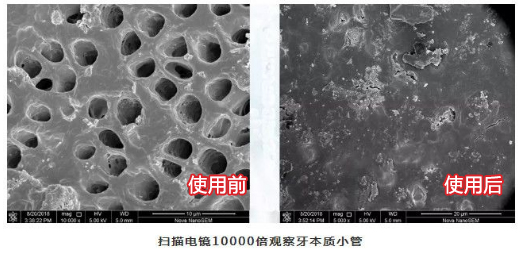

这是测试人员牙齿表面的显微镜图,在使用3天后,牙齿表面的小孔已经基本填补完成!太厉害了!

能修复牙釉质,还能增强牙齿的坚固性,我们通过一个实验来看看效果。

我们看了显微镜下的对比图:涂了含有羟基磷灰石成分的欧志姆牙膏以后,鸡蛋外壳密度明星增加,而涂了普通牙膏的鸡蛋,密度依然很大孔隙。